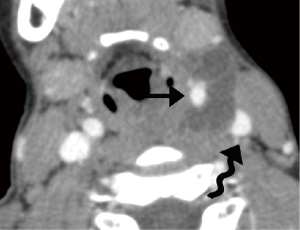

Schwannomas are benign tumors arising from Schwann cells surrounding peripheral nerves. Schwannomas in the carotid space most commonly stem from the vagus nerve. The tumor is usually a sharply demarcated round or oval mass with hypo-, iso-, or hyper-attenuation. Cystic degeneration, xanthomatous change, or areas of relative hypocellularity adjacent to densely cellular or collagenous regions usually contribute to heterogeneity of the tumor (Figure 1) (9,10). Schwannomas are hypovascular tumors, but in dynamic scans, they can show marked enhancement due to pooling of contrast agent resulting from poor venous drainage (11). More often, schwannomas demonstrate a variable degree of enhancement, most commonly patchy enhancement (Figures 2-7).

Due to its location between the vein and artery in the carotid space, schwannomas of the vagus nerve tend to separate the artery and vein, usually displacing the CCA/ICA medially and the IJV laterally (Figures 2,3) (12). Some schwannomas of the vagus nerve may displace the IJV and ICA/CCA in a posterior direction without splaying them and there is usually separation between the artery and vein (Figure 4). The cervical sympathetic chain runs in a fascial reflection posterior and slightly medial to the carotid space. Hence, schwannomas of the sympathetic chain tend to displace the IJV and CCA/ICA together, usually anteriorly and laterally (Figure 5) (5). A large schwannoma of the sympathetic chain may distort the surrounding anatomy and result in a posterior displacement of the carotid vessels without separation of the artery and vein (Figure 6) (13,14). Occasionally, a schwannoma of the cervical sympathetic chain may splay the internal and external carotid arteries at the carotid bifurcation but without encasing the arteries (Figure 7) (5). In these regards, the position of the tumor relating to the vessels in the carotid space is more important than the direction of vascular displacement. There has also been a reported case of schwannoma arising from the glossopharyngeal nerve in the carotid space causing posterior displacement of the ICA (15).